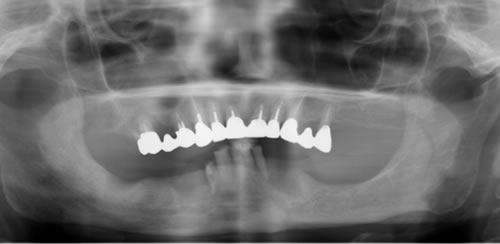

奥歯に骨がないので、オールオン4で即時荷重(インプラント手術をした日に仮歯がはいる)をおこないました。